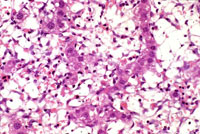

An Ito cell tumor that has replaced much of the normal hepatic parenchyma without distorting the normal contour of the liver; higher magnification shows fat-filled and stellate cells in the hepatic sinusoids.

The proliferating stellate cells have a myxomatous appearance in some areas and have caused atrophy of hepatic cords.